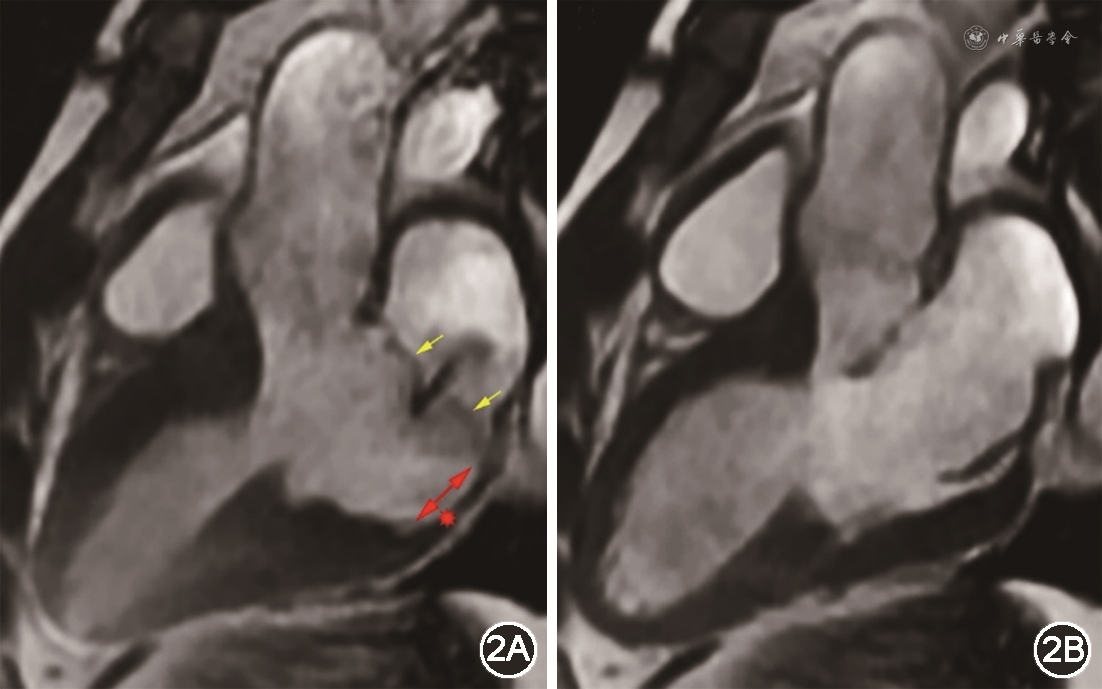

MAD的影像学表现为:左心房壁-二尖瓣环后叶连接点与左心室后侧壁顶部之间存在不同程度的分离,可伴有后叶二尖瓣环的收缩期外向运动,即卷曲运动(curling motion)。影像学检查时,在胸骨旁长轴切面、心室收缩末期最易观察到MAD。心室舒张时左心室游离壁顶部正好位于二尖瓣后叶附着点下方,二者呈纵向线性毗邻关系,MAD可能会被掩盖;当左心室后外侧壁心肌收缩时,二尖瓣环滑动使后叶附着点与左心室游离壁顶部的距离拉大,形成可见的MAD,分离距离从1 mm到>10 mm不等(图2)。文献报道中MAD的诊断标准并不统一,但一般认为分离距离>2 mm即可诊断[1,4,6, 7],但是否所有符合诊断标准的MAD都有临床意义尚不明确。经胸超声(transthoracic echocardiography,TTE)、经食管超声(transesophageal echocardiography,TEE)和心脏磁共振(cardiac magnetic resonance,CMR)等无创影像学检查是诊断MAD的主要方法,但目前作为参考标准的影像学技术尚未确定。TTE是诊断MAD的重要工具,其简单有效、成本低廉,可以很好地评估二尖瓣形态和二尖瓣反流,但容易受声窗不足、二尖瓣钙化、空间分辨率较低和操作者经验的影响,导致MAD的漏诊率较高。TEE对MAD的检出率较TTE稍高,但其主要应用于外科术前评估二尖瓣的解剖结构,且TEE为半侵入性检查,因此在临床上并不常规应用。CMR的空间分辨率高,可清晰辨别相邻的组织结构,因此能更敏感地发现MAD,其对MAD的检出率最高,可作为诊断MAD的金标准,同时CMR还可以通过延迟钆增强成像识别可能并存的心肌纤维化[6]。有研究报道,心脏CT(cardiac computed tomography,CCT)也可用于检测MAD[8],CCT有很高的空间分辨率,可进行各向同性三维图像重建,因此能很好地识别MAD,且CCT较CMR更为普及、检查过程省时简便,应用于MAD的筛查和诊断有较好前景。